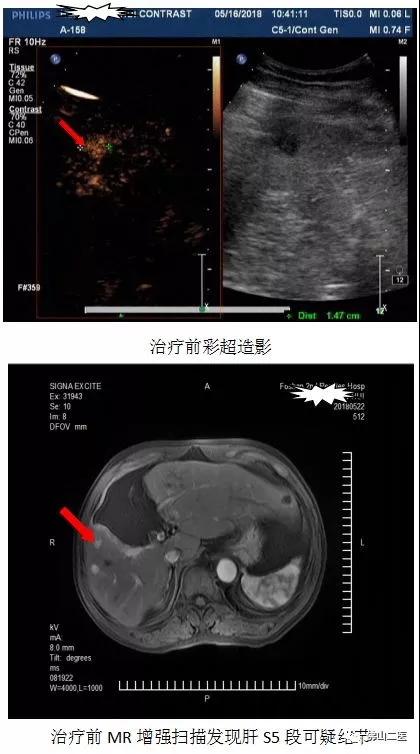

肝脏B超造影检查立刻进行。结果发现黄伯肝S5包膜下低回声结节,约15*11mm,性质待查,结合超声造影,考虑恶性结节(HCC)可能;肝S6包膜下低回声,约14*10mm,性质待查,结合超声造影,考虑良性结节(增生结节)可能。

“这很有可能就是肝癌复发!”黄小青立刻指示进一步做腹部MR平扫+增强检查,以佐证病情。

“肝S5、S6两个类圆形异常信号肿块影,考虑残存肝癌结节或复发可能性大,腹膜后散在肿大淋巴结。”腹部MR平扫+增强回报示。血液肿瘤科即联系MR赵继泉主任医师会诊,亦考虑肝S5结节高度怀疑肝癌结节,肝S6结节良性结节可能性更大。

在B超陆培明主任医师及陈大卫主治医师的大力配合下,血液肿瘤科黄小青主任和马庆辉主治医师为黄伯顺利完成了手术,术中B超造影显示肿瘤消融完全;术后24小时黄伯即下床活动自如;术后病理证实,结合免疫组化及形态学,符合肝细胞癌。